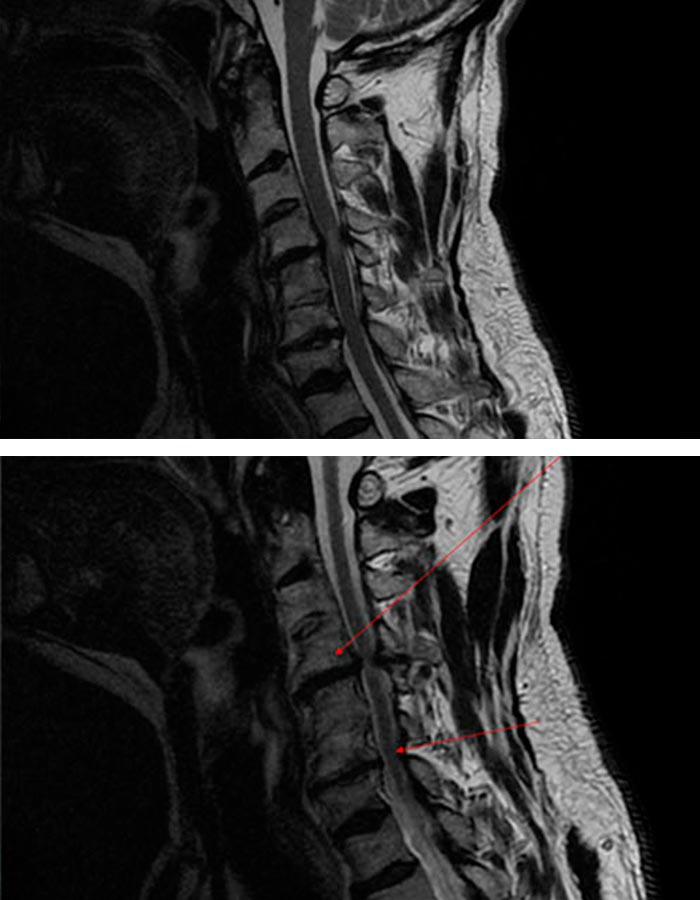

Tras realizar la exploración clínica correcta, así como analizar el estudio RMN y RX, se objetiva una estenosis de canal severa a nivel de 4º y 5º de las vertebras cervicales. También se observa una estenosis de forámenes bilateralmente entre las vértebras 6ª y 7ª, además de una hernia discal cervical en C4C5.

Al nivel de C5C6 el paciente presenta una fusión natural que probablemente haya sido la causa del deterioro progresivo en los niveles adyacentes y del intenso dolor que sufre.

cirugia avanzada de columna cervical